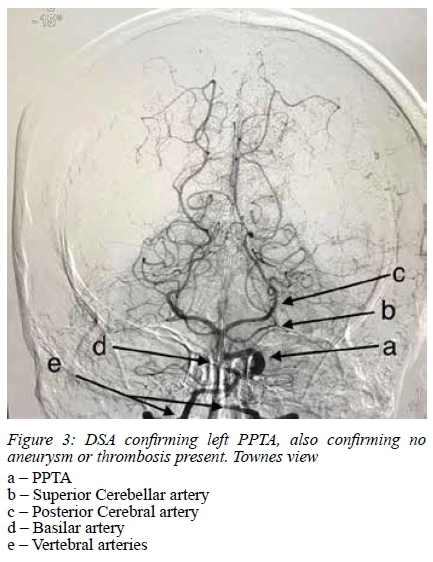

Formal Four-vessel Digital Subtraction Angiography (DSA) also confirmed a left PPTA (Figure 4).

A well-defined, rounded lesion similar to a vessel (observing the coronal section of the ICA in the cavernous sinus) should lead to suspicions of PPTA.4 Failure to recognize such anomalous vessels within the sella may lead to serious complications during transsphenoidal surgery. The DSA images suggest the patient has a Saltzman type 1 PPTA, where the PCommA is absent or poorly opacified.